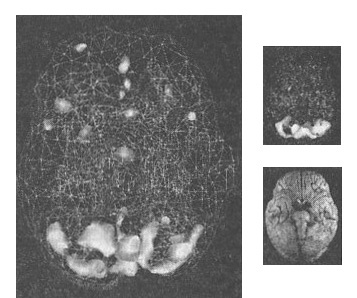

Познакомившись с Джеком, я увидел, что под озлобленной внешностью скрывается добрый мальчик. Томография ОЭКТ показала значительно повышенную активность по всему мозгу (рис. 8.1 и 8.2).

Мозг Джека

Рис. 8.1 До лечения

Повышенная в целом активность («кольцо огня»)

Рис. 8.2 После лечения

Активность мозга нормализована

Мы называем рисунок таких снимков «кольцом огня». Снимок привлек внимание Джека, и он впервые заинтересовался своим лечением, стал задавать вопросы о томограмме и о своем мозге. На этой волне интереса он согласился принимать пищевые добавки и рыбий жир, стал работать со мной, чтобы научиться контролировать свой характер и лучше вести себя дома и в школе. Через четыре месяца после начала лечения мы заказали повторный скан. Его мозг, как и было ясно по его новому доброжелательному поведению, значительно успокоился. Сбалансировав мозг Джека, мы смогли изменить его жизнь.